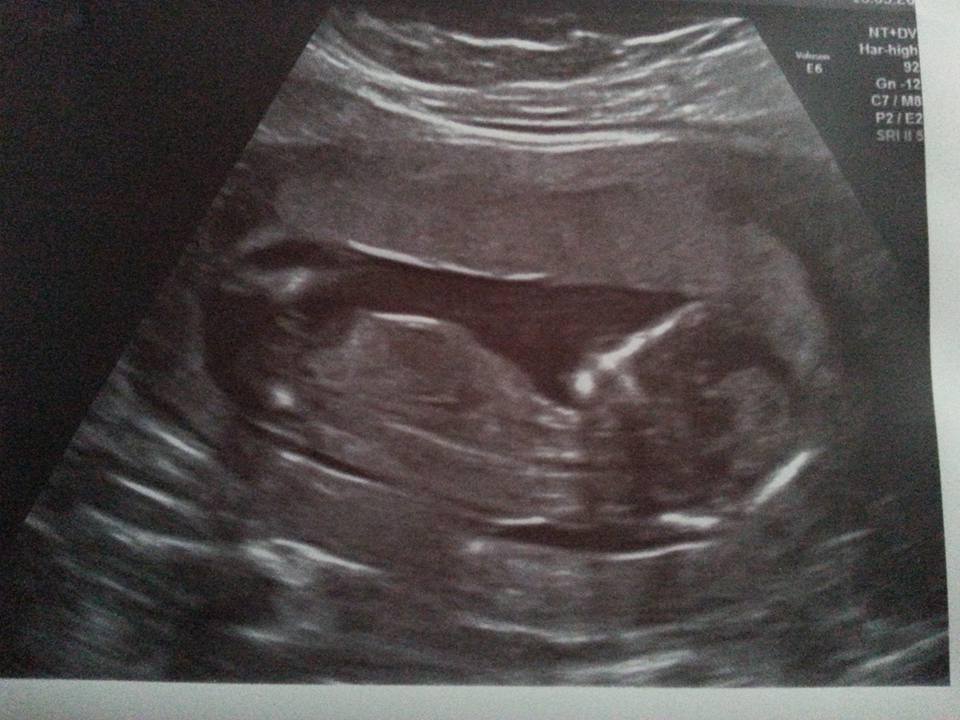

Byla jsem ve stredu. Dle ms 6+5, podle embrya 7+2 a srdicko bilo jak dive.